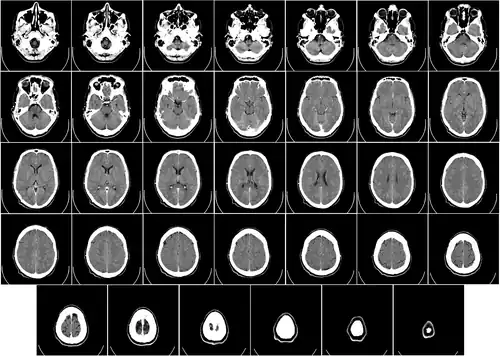

Компьютерная томограмма головного мозга